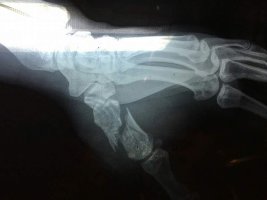

손가락골절 손등 골절

중요한 신체부위이기 때문에 골절 등의 손상을 입게될 경우 상당한 불편함이 남게될 수 있습니다 손가락골절이 발생하였다면 보험에서는 후유장해를 검토할 수 있습니다 다만 본인이 가입한 개인보험에

손가락골절로 진단받고 증상이 심한 경우엔 수술적 치료를 감수해야할 수도 있습니다 문제는 수술 후 발생할 수 있는 후.유.증 인데요 후유증으로 통증이 생길 수 있고 손가락을 구부렸다 폈다하는데